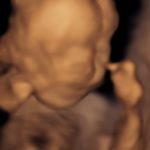

4D/5D/HD Ultrasound Gallery

Gallery